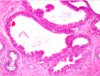

What type of breast cancer is depicted? [1]

ductal carcinoma in situ (DCIS)